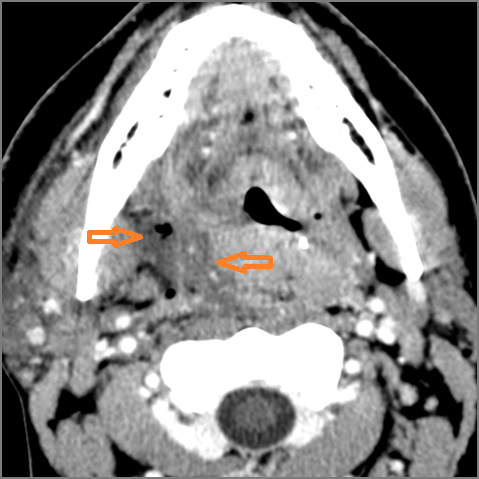

There is edema within the fat of the adjacent parapharyngeal space.

There is an abscess within the fat of the adjacent parapharyngeal space.

There is edema within the fat of the adjacent retropharyngeal space.

There is an abscess within the fat of the adjacent retropharyngeal space.